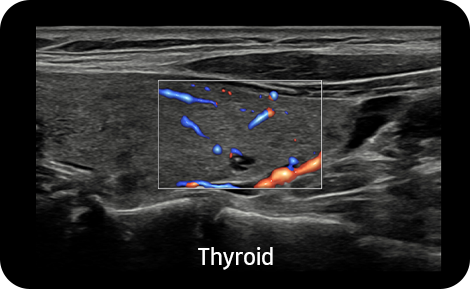

Show blood flow in vessels

in a 3D like display

LumiFlow™ ¹ is a function that visualizes blood flow in 3 dimensional-like to help understand the structure of blood flow and small vessels intuitively.

Examine peripheral vessels with

directional power Doppler

S-Flow™, a directional Power Doppler imaging technology, can help to detect even the peripheral blood vessels. It enables accurate diagnosis when the blood flow examination is especially difficult.